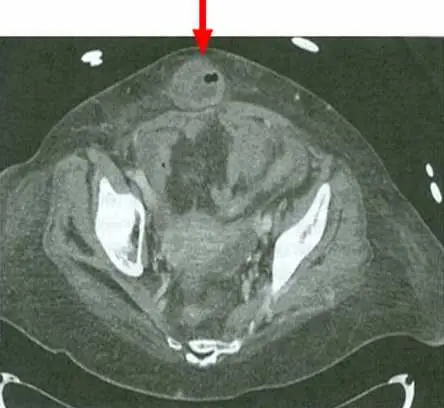

68 歲女性因肚臍周圍疼痛合併噁心嘔吐至急診,理學檢查發現體溫 37.5 ℃,且肚臍周圍有壓疼,血液檢查 WBC :14500/µL ,分類 segment :85% ,腹部電腦斷層結果如圖,最可能的診斷為何?

CT 橫切面(axial section)顯示骨盆腔至下腹部層面,紅色箭頭指向前腹壁正中線(midline)臍部位置,可見一個小型囊袋狀結構自腹壁缺損處向外突出,內含脂肪密度組織(omental fat),周圍可見輕微脂肪浸潤(fat stranding),提示為臍疝或旁臍疝(umbilical/paraumbilical hernia),且有嵌頓(incarceration)跡象。腹腔內其他器官(如闌尾區域、結腸)於此切面未見明顯炎性改變,未見闌尾腫大或憩室炎影像。